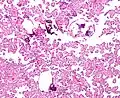

Histopathology

The tumor is neuroectodermal in origin and similar in structure to a normal choroid plexus. They may be created by epithelial cells of the choroid plexus. Papillary fronds lined by bland columnar epithelium are visible under the microscope. Normal absences include mitotic activity, nuclear pleomorphism, and necrosis.[10] Tumors have positive immunohistochemistry for cytokeratin, vimentin, podoplanin, and S-100.[11] Up to 20% of choroid plexus papilloma patients may test positive for glial fibrillary acidic protein (GFAP).[12] Studies have found that fourth ventricle cancers express more S100 than lateral ventricle tumors, and older patients (over 20 years) express more GFAP and transthyretin than younger patients.[13] Some individuals with choroid plexus papilloma have germline TP53 gene mutations, according to genetic analyses.[14] These cancers rarely exhibit nuclear p53 protein positivity. Aicardi syndrome, hypomelanosis of Ito, and 9p duplication are syndromic correlations of choroid plexus papilloma.

Micrograph of a choroid plexus papilloma. H&E stain.

Plexuspapillom Detail

Plexuspapillom Overview